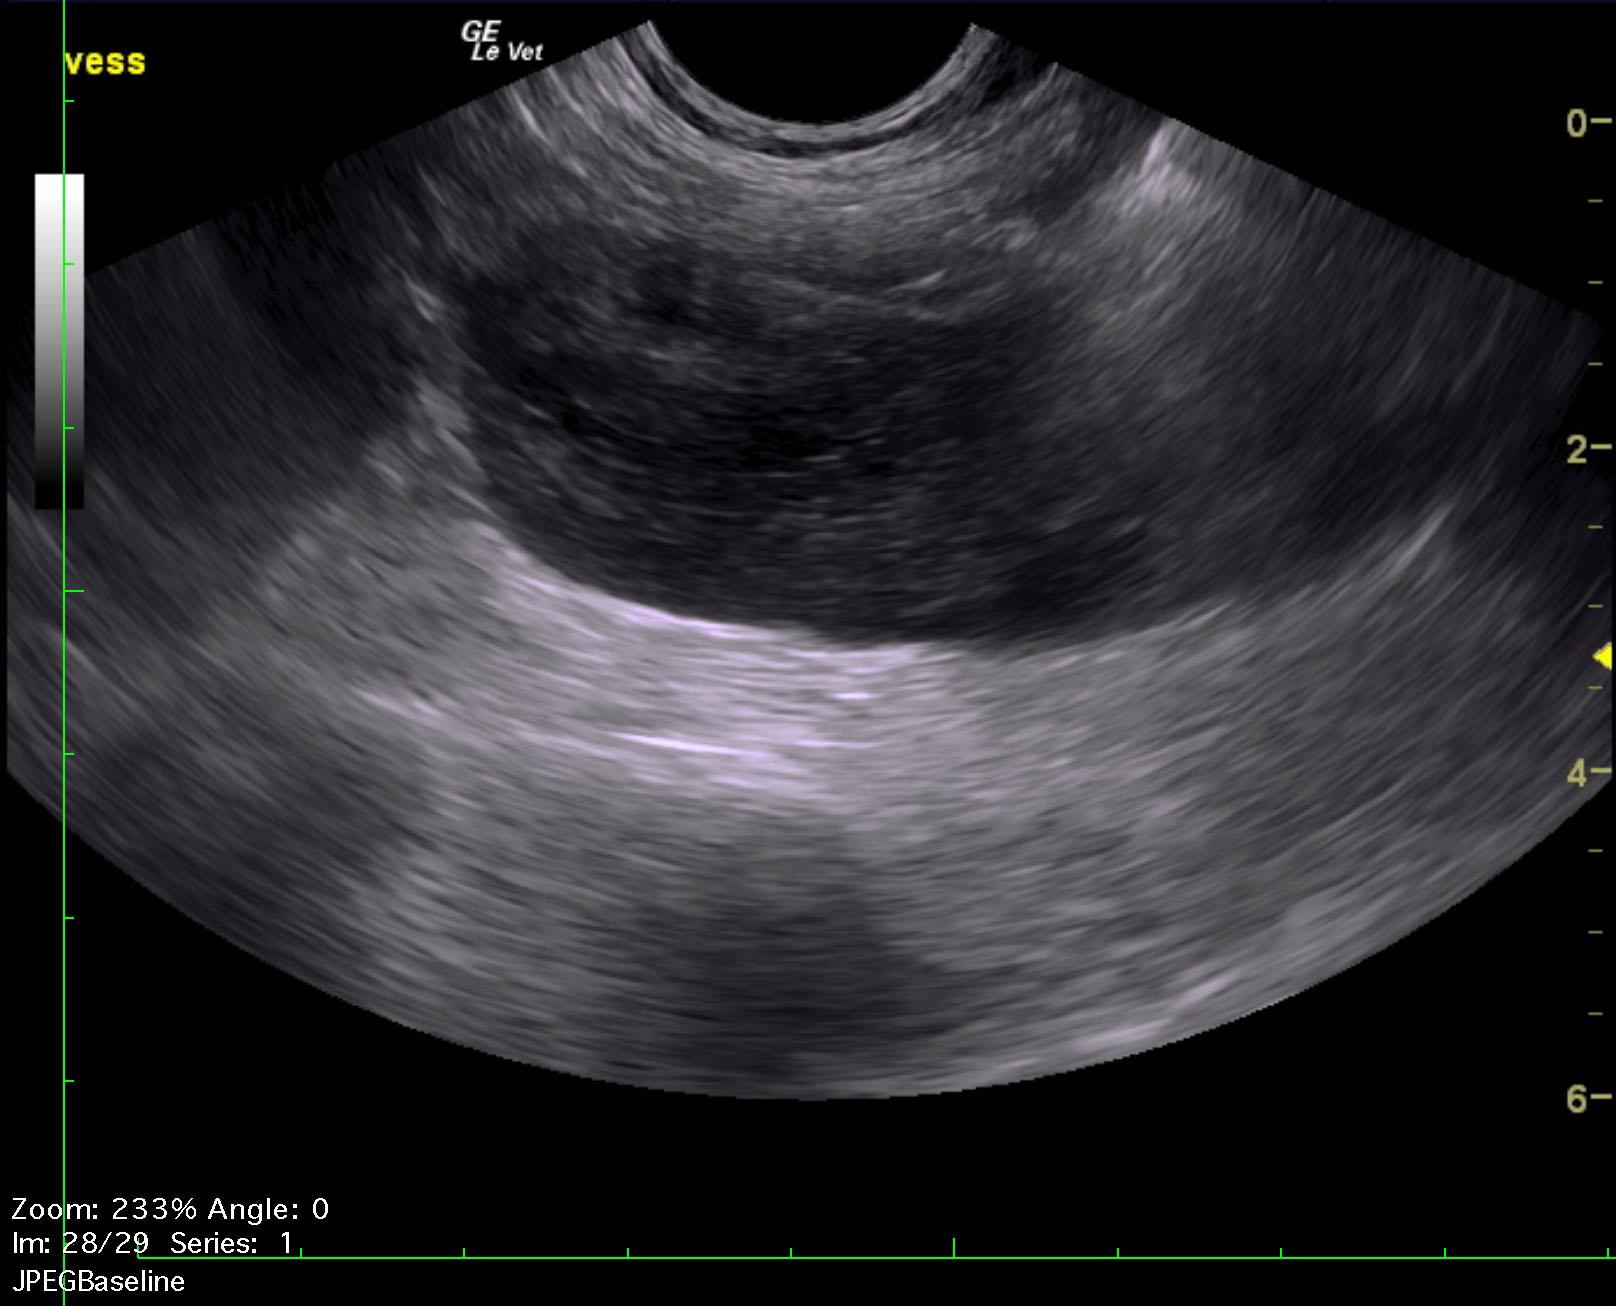

A 1-year-old NM German shepherd with a history of PU/PD and hypercalcemia was presented for evaluation of lethargy, weight loss, and anorexia. Left-sided nephromegaly was present on survey radiographs. Abnormalities on serum biochemistry were hypercalcemia, azotemia, and mildly elevated ALT activity.